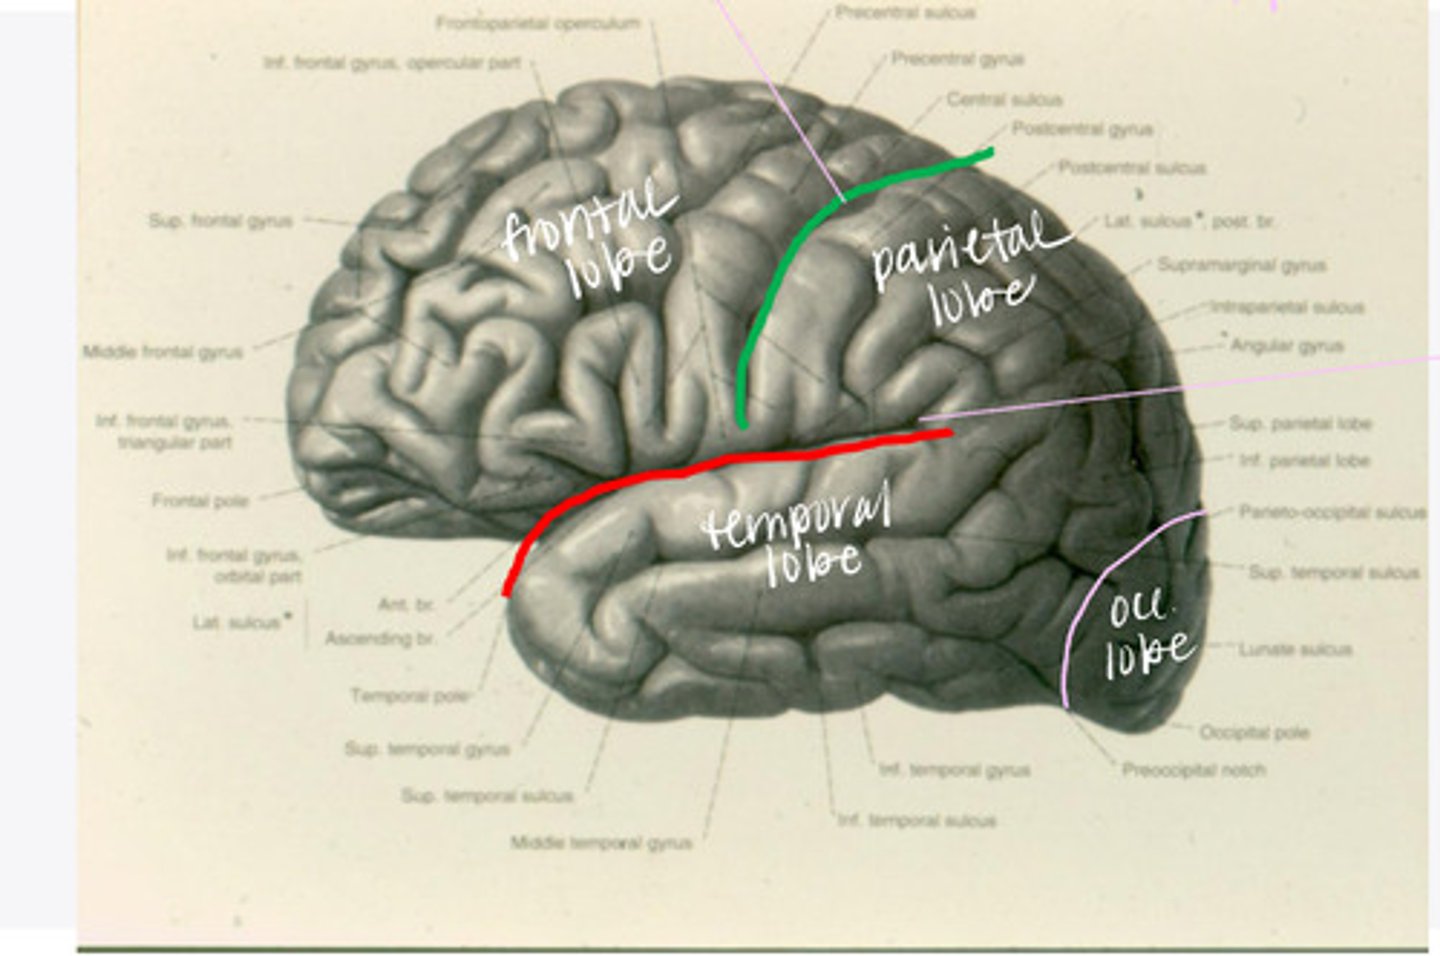

-frontal

-parietal

-temporal

-occipital

What are the 4 lobes of the brain?

central sulcus

What sulcus differentiates the frontal from the parietal lobe?

lateral sulcus

What sulcus differentiates the frontal from the temporal lobe?

The frontal lobe is divided into what 4 gyri?

What are the 3 divisions of the inferior frontal gyrus?

-post-central gyrus

-superior parietal lobule

-inferior parietal lobule

What are the divisions of the parietal lobe?

-supramarginal gyrus

-angular gyrus

What are the divisions of the inferior parietal lobule?

-superior temporal

-inferior temporal

What are the 2 major sulci of the temporal lobe (on lateral view)?

-superior temporal

-middle temporal

-inferior temporal

What are the 3 major gyri of the temporal lobe (on lateral view)?

everything posterior to the line connecting the parietooccipital sulcus and the preoccipital notch

Where is the occipital lobe located in a lateral view of the brain?